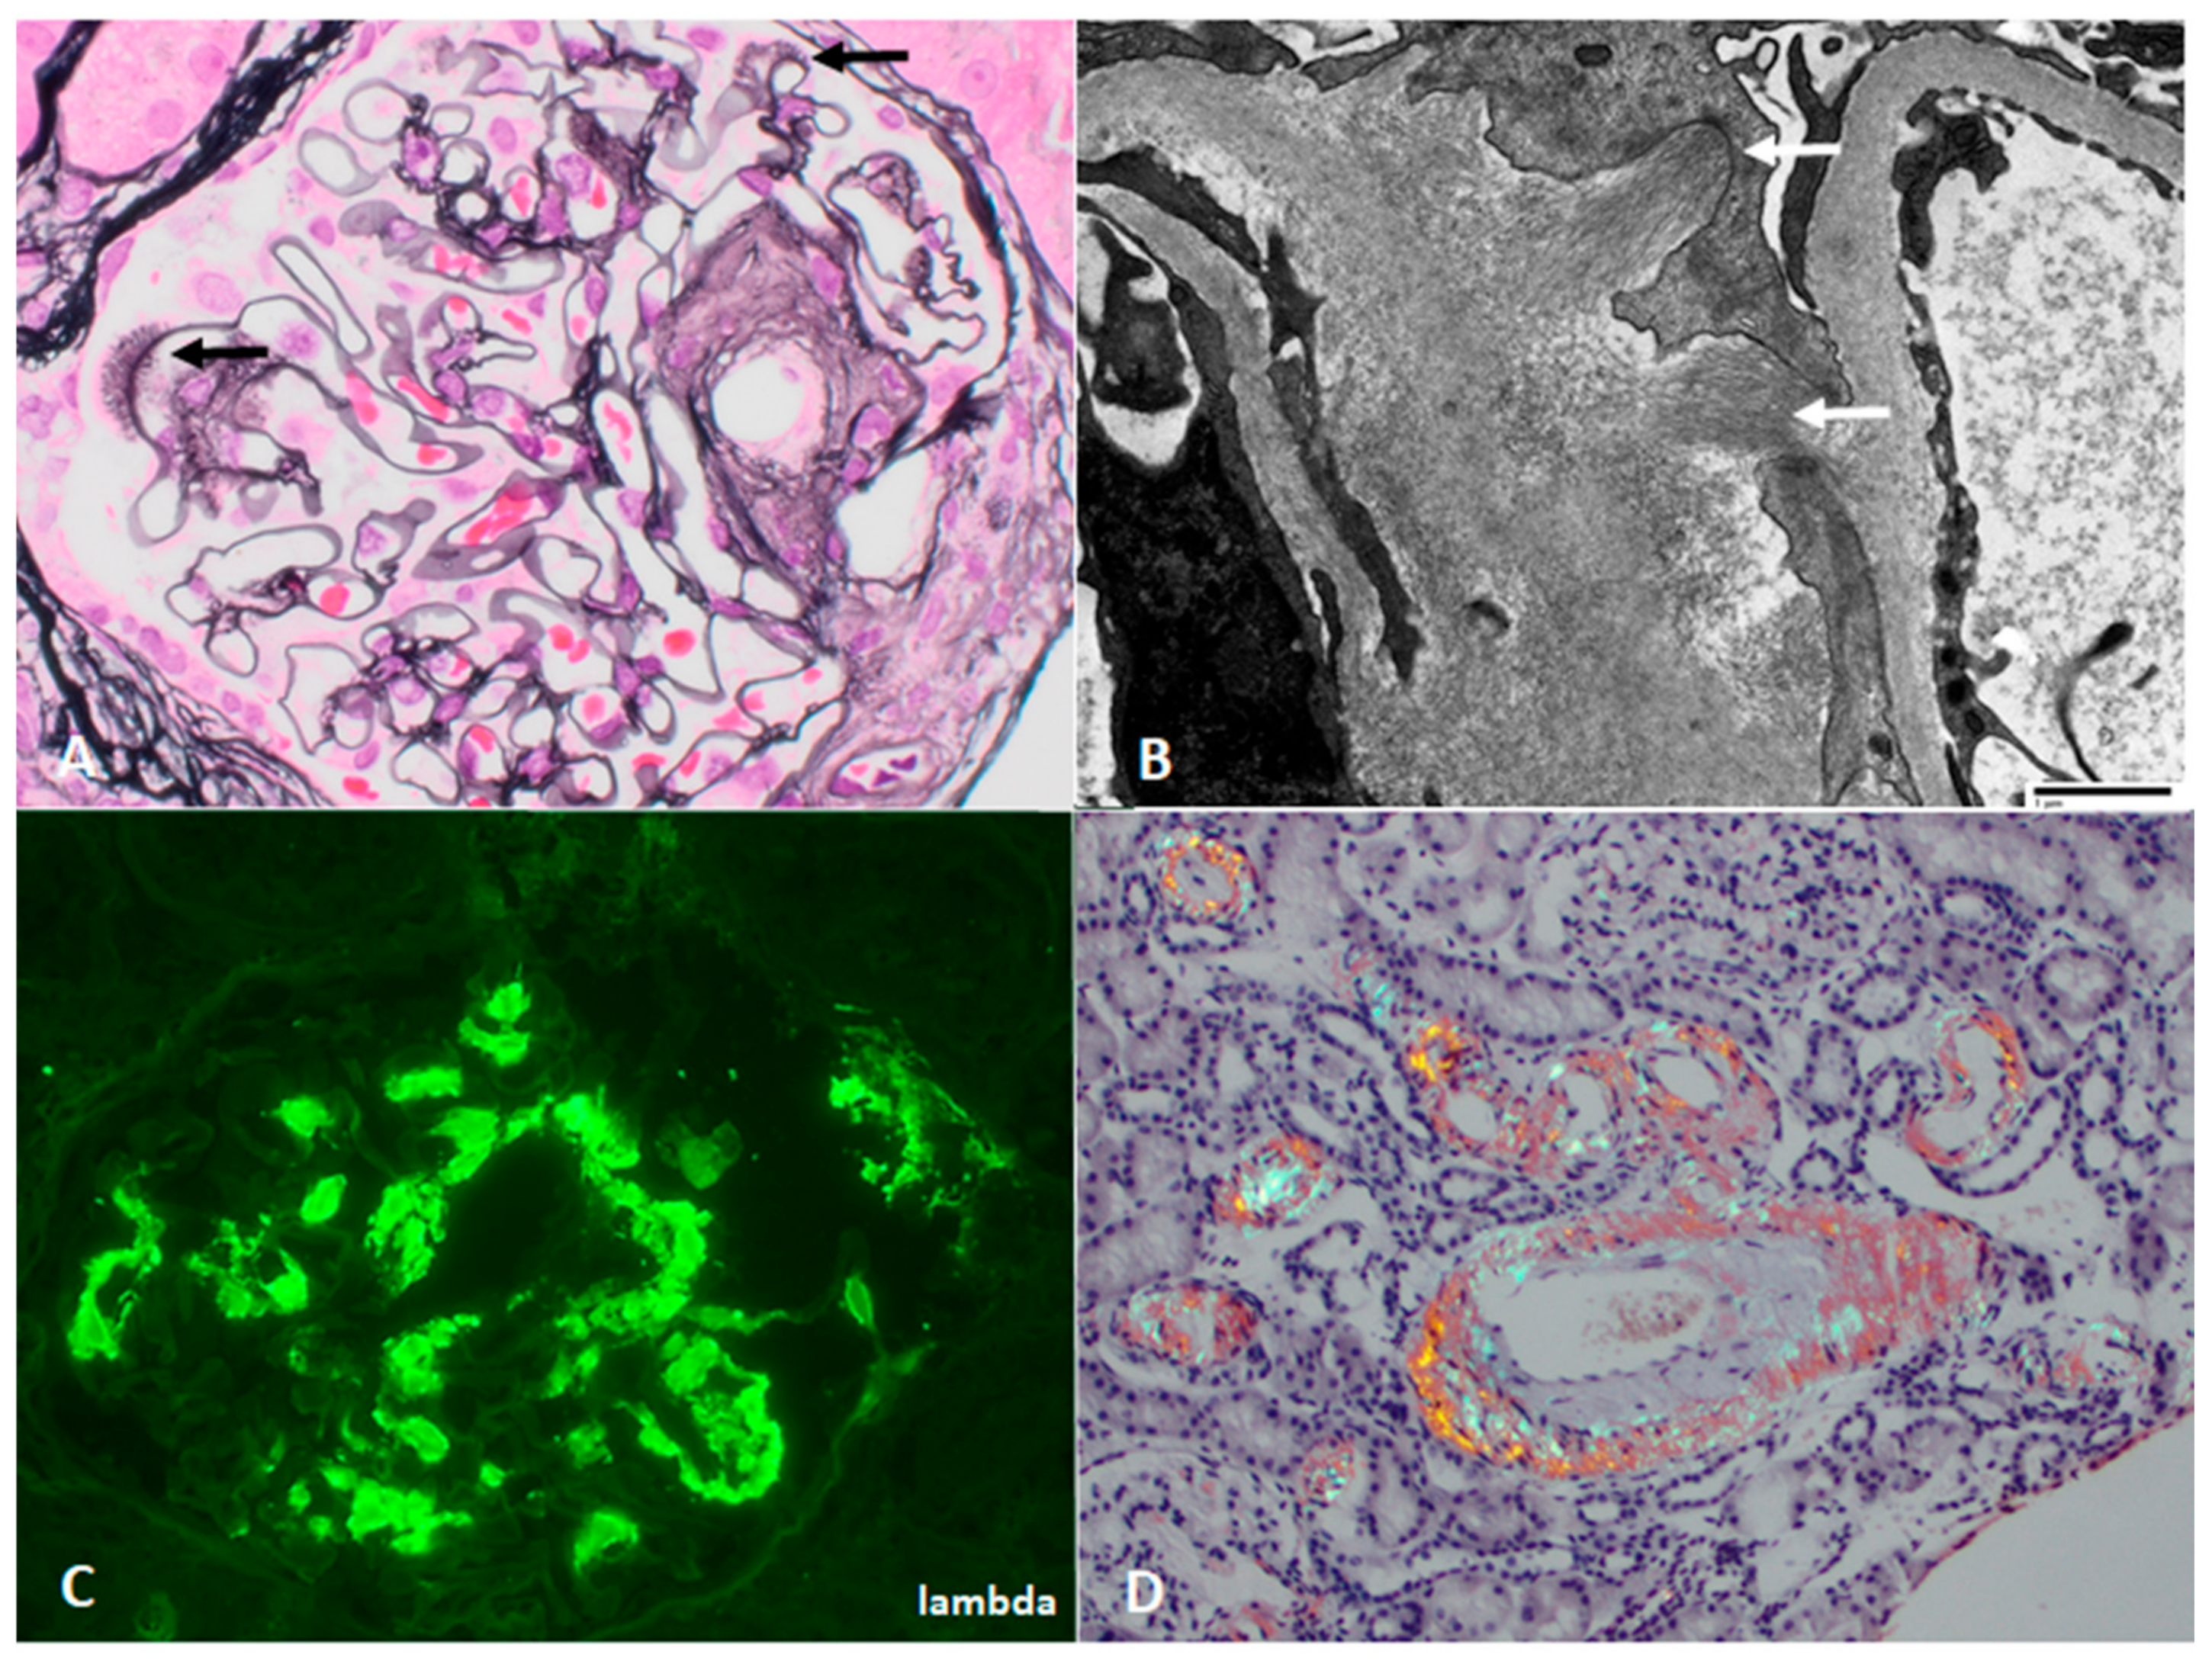

| Immunotactoid glomerulopathy | Endocapillary to MPGN pattern, membranous | 66% monoclonal, often IgG1 kappa | Fibrils with hollow cores and parallel arrays, ~30 nm | Exclude cryoglobulinemia. IgG subclasses confirm IgG monoclonality. DNAJB9 negative | Unknown |

| Cryoglobulinemic glomerulonephritis | Endocapillary to MPGN pattern | Glomerular staining for IgG, IgM, and light chain(s) | Subendothelial, mesangial deposits, some with microtubular organized substructure | IgG subclasses confirm IgG monoclonality. Substructural organization in isolation is insensitive to identify cryoGN. | Type I: temperature and concentration-dependent aggregation of monoclonal protein, with small vessel occlusion and injury Type II: Monoclonal IgM directed against Fc portion of polyclonal IgG |